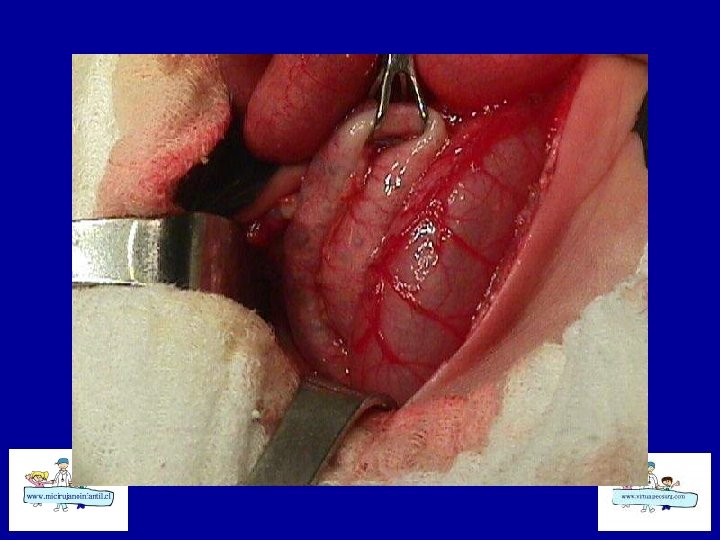

ECN-TRATAMIENTO • Quirúrgico: Laparotomías amplias • Drenaje peritoneal • Aseo abdominal y resección de asas necróticas • Ostomía vs Cierre primario • Second Loock

ECN- Indicaciones de cirugía • Absoluta: Perforación intestinal • Relativas: Deterioro estado general, Masa palpable? , celulitis de pared, Gas Porta? , obstrucción intestinal, Paracentesis alterada, Asa centinela en Rx abdomen simple. • 25 a 30 % de ECN requieren cirugía. • 19 % en los > 1500 gr y 41 % en los < 1500 gr.